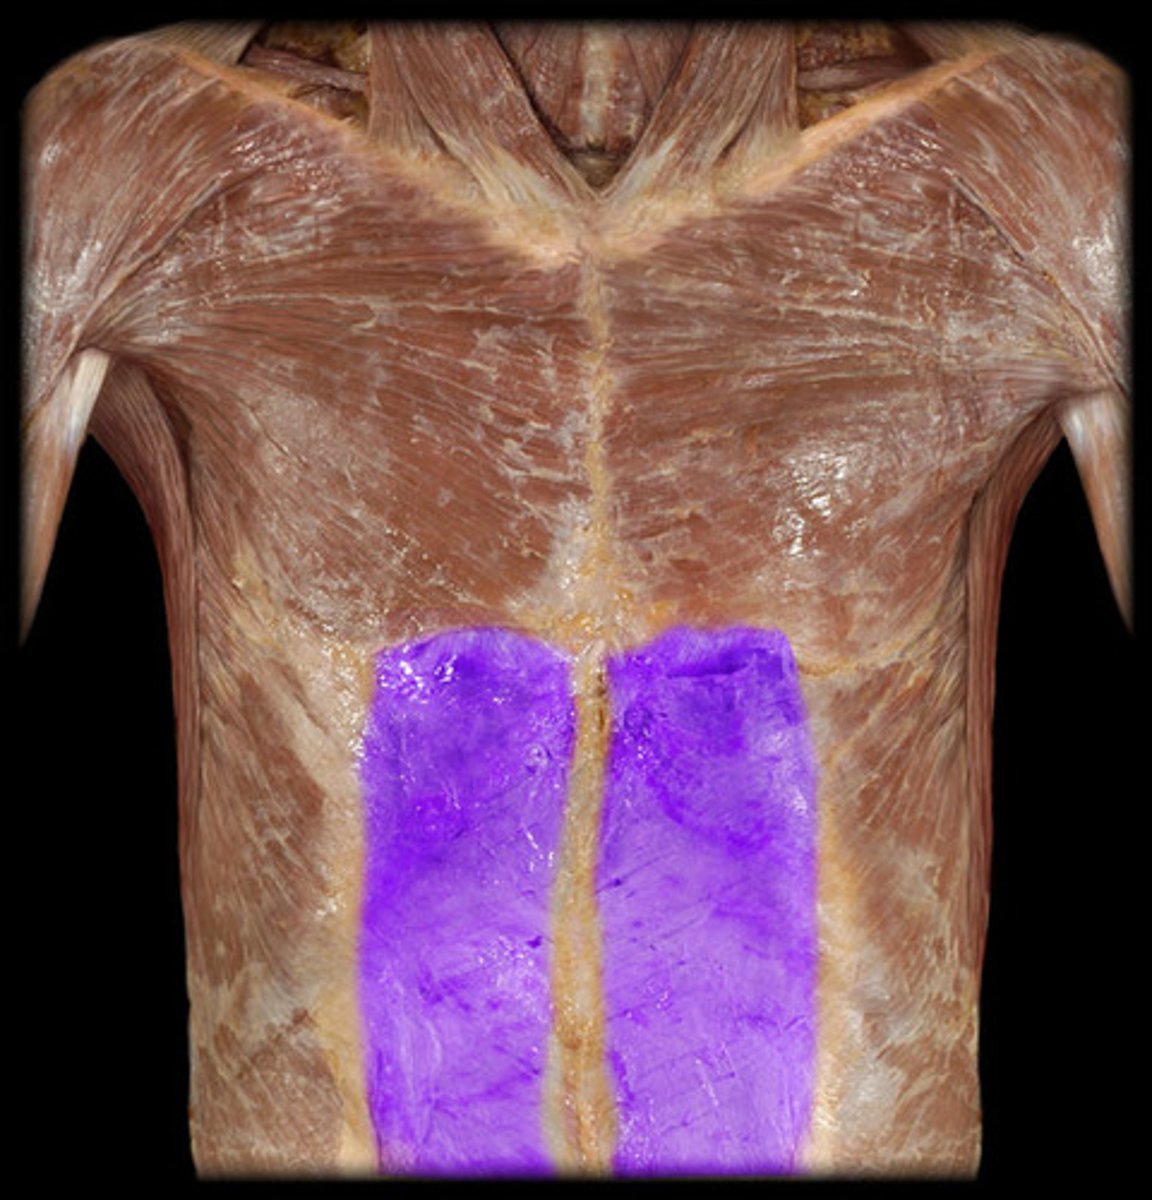

rectus abdominus

tendinous insertions

rectus sheath